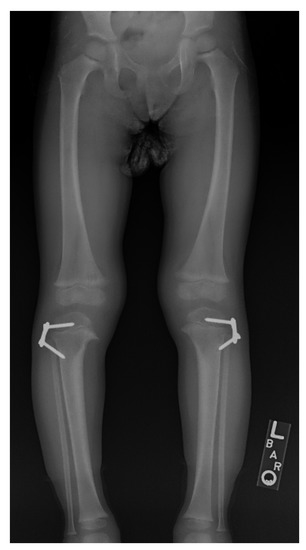

11. Hemi-Epiphysiodesis

12. Physeal Arrest Resection